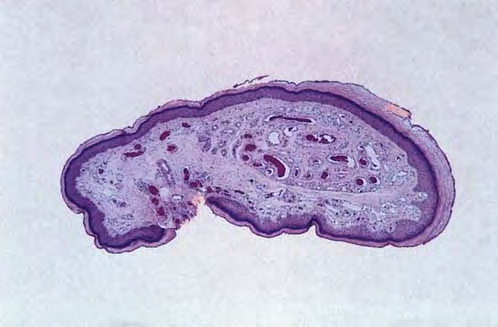

Atlas of skin histopathology

Artefacts= افة جلدية مفتعلة